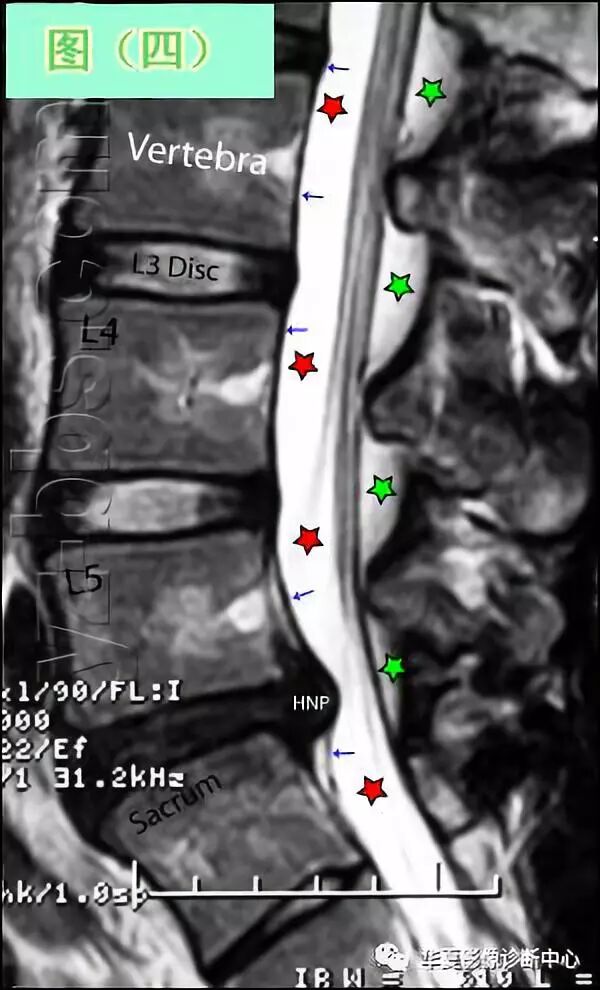

图(四)是脊柱腰区的侧视图,或称矢状面图像。

请注意此影像是介于T2和T1之间,被称作质子密度像,对于判断椎间盘突出是否穿破后纵韧带(PLL)是最好的图像。象T1像一样,它用的是高磁性,所以细微部分表现得出奇地好。

先看其基本结构:位于椎体之间的椎间盘应是白色的(含水多)。注意黑颜色(脱水的)的L5椎间盘(L5与骶骨之间的椎间盘),这代表了中度到重度的退化性椎间盘病。后纵韧带(PLL小蓝箭头)在图像中表现为沿着每个椎体及椎间盘后缘垂直向下的黑线。

有意思的是,尽管此病人有一个9mm的椎间盘突出(HNP),骨质有一定的翘起,在椎间盘平面以上可见髓核物,但后纵韧带仍然包容着突出的髓核物而没有游离出。

这种情况在学术上被称作一个大的包容性椎间盘突出。 硬膜囊(红星)表现为“超白色”结构,填充在椎体后方的中央椎管内。此囊袋内有可自由浮动的由运动神经纤椎及感觉神经纤维共同组成的脊神经根(马尾)。 黄韧带(绿星)位于每个椎骨之间,增强脊柱的稳定性。此结构可变大或增厚,助长年长者易患的中央型椎管狭窄的形成。